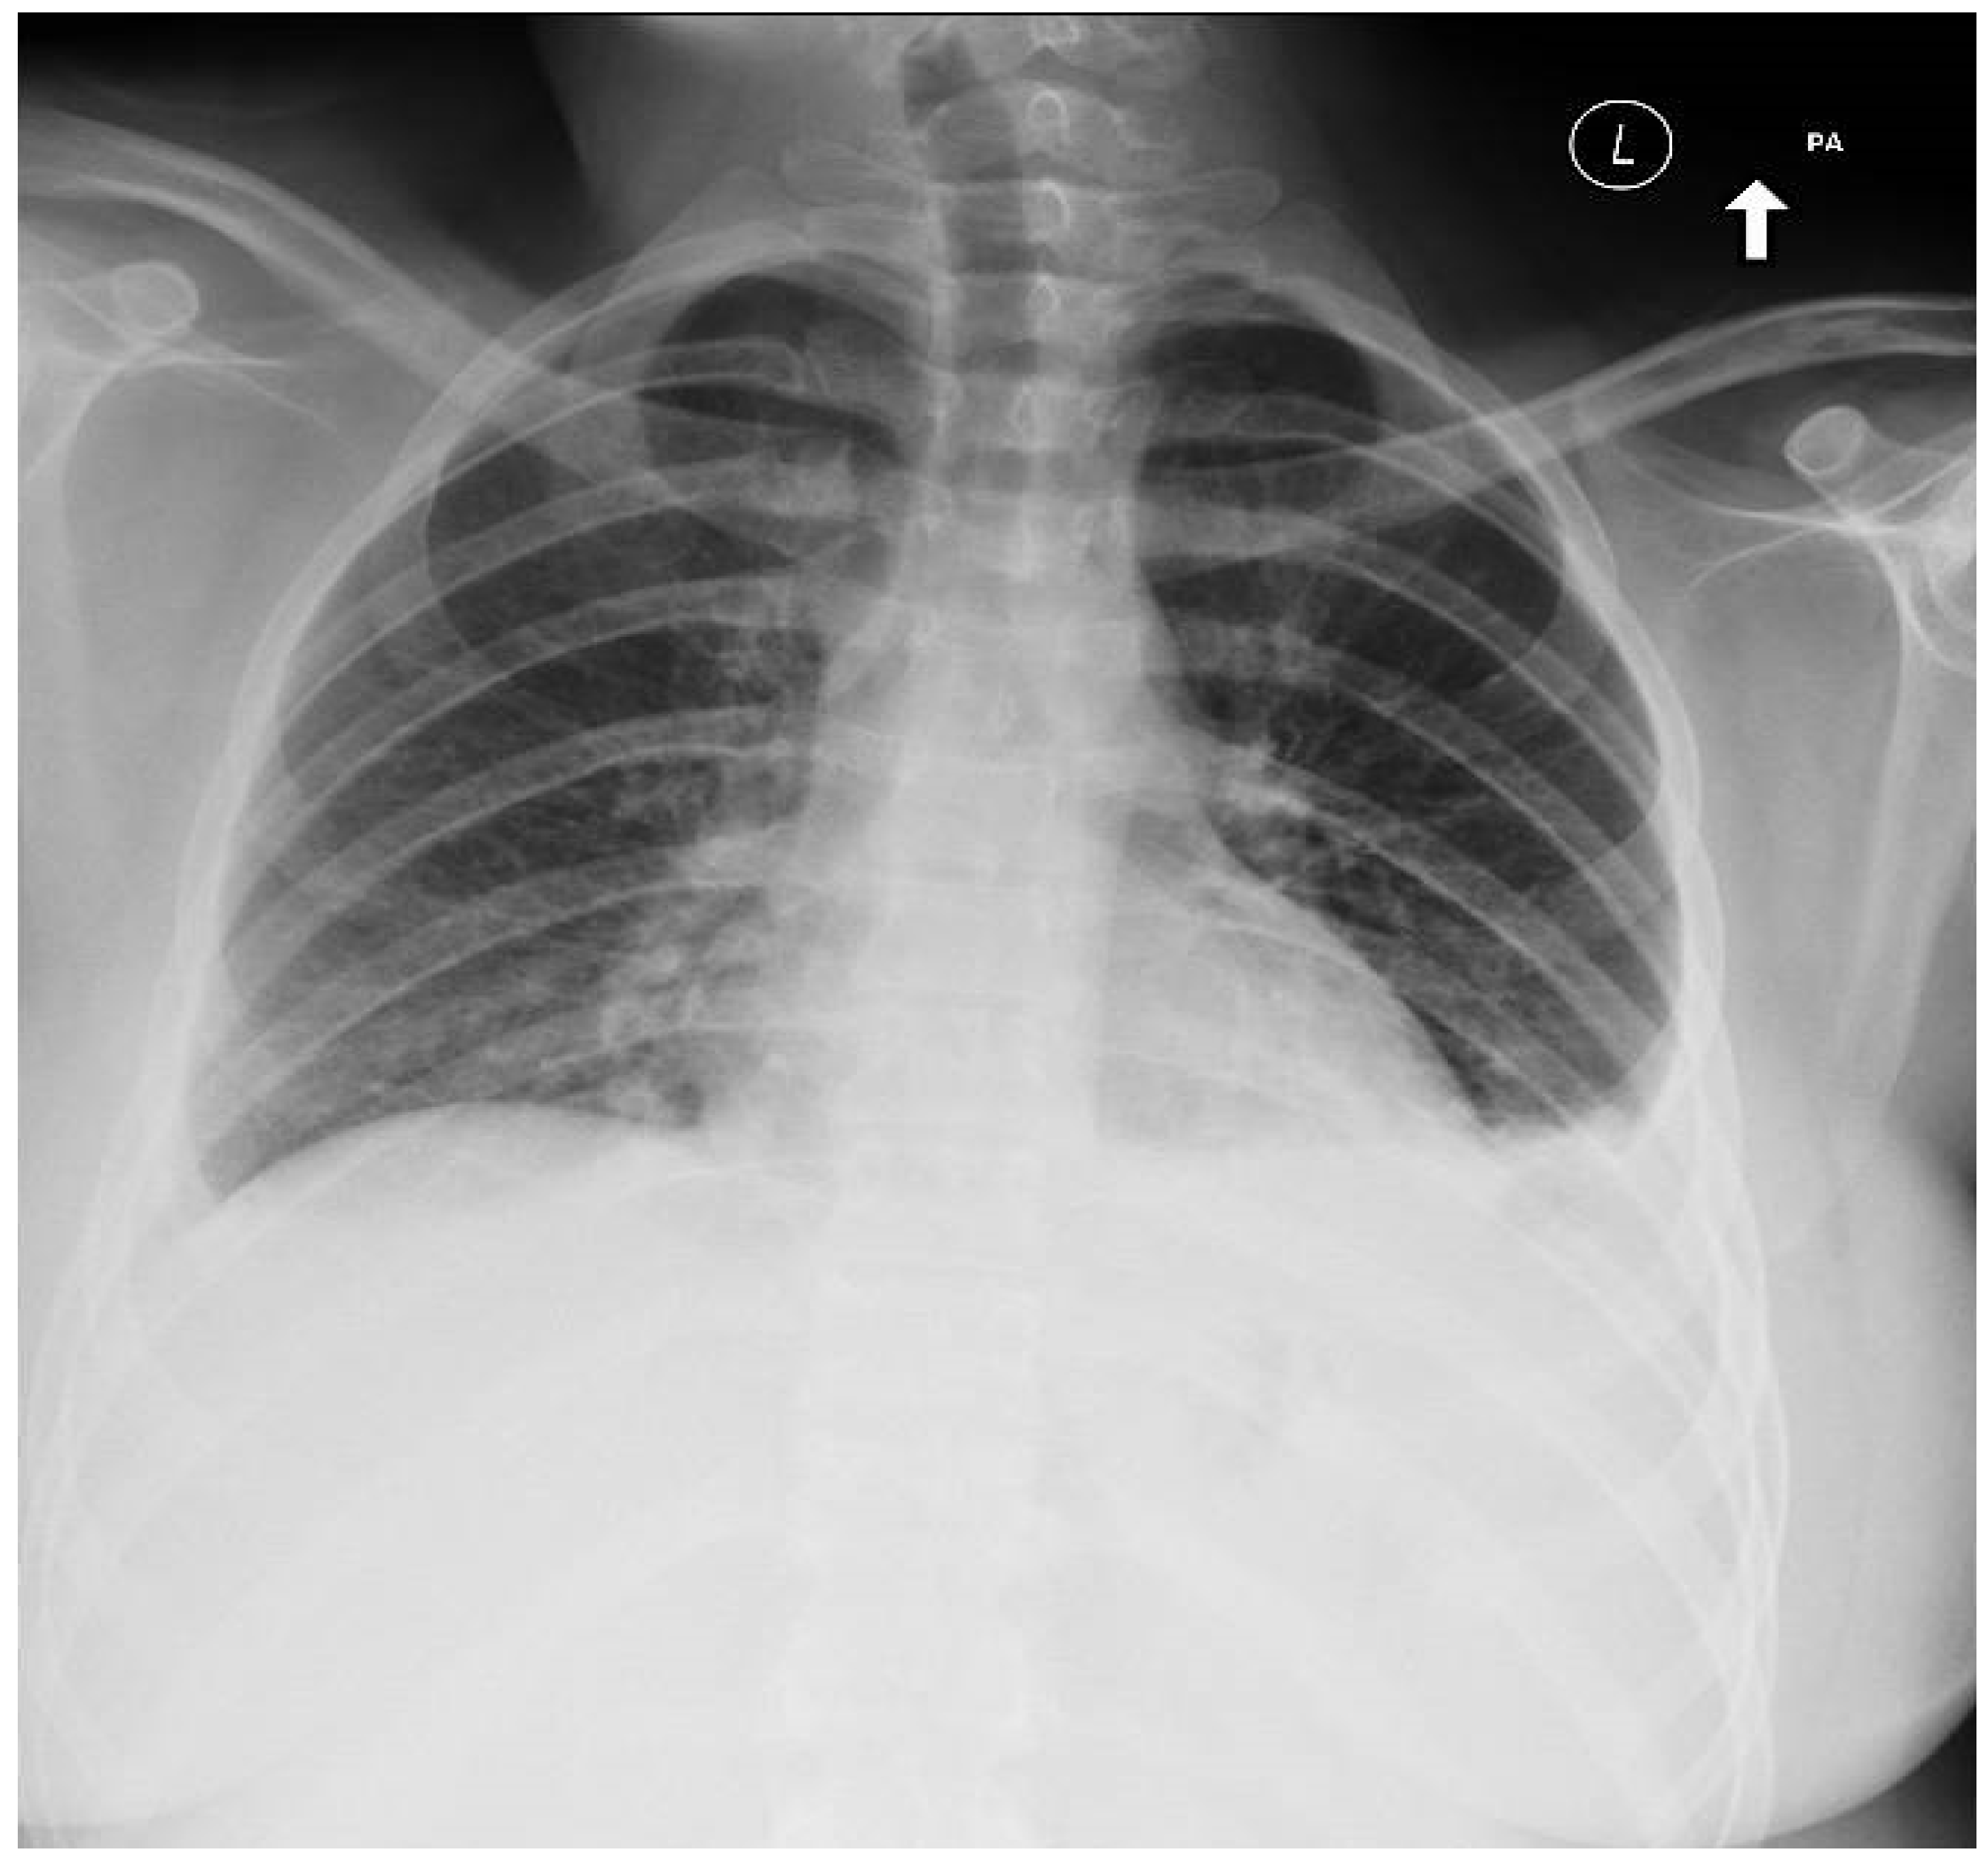

Unexplained Dyspnea in a Young Adult with Epstein–Barr Virus Infectious Mononucleosis: Pulmonary Involvement or Co-Infection with Mycoplasma pneumoniae Pneumonia?

2. Case